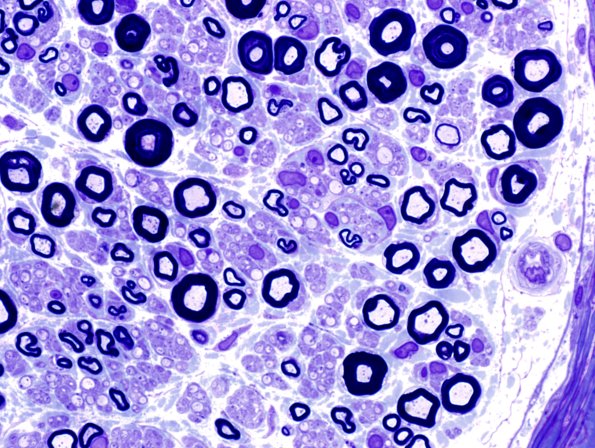

Washington University Experience | PERIPHERAL NEUROPATHY | 6 AXONAL DEMYELINATION (BASIC PROCESS) | 6A3 Demyelination (Case 6) Plastic 12.jpg

In this section of a different fascicle there appears to be a markedly increased number of demyelinated axons; however, they are so numerous and a number are back to back suggesting artifactual dilatation of unmyelinated axons as well as true demyelinated forms. (Toluidine blue stained one micron thick plastic section)